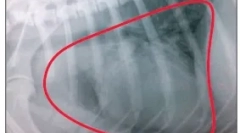

Diagnostika

O primárnej inšpekcii veterinárneho lekára hodnotí neoplazmus, pokiaľ ide o jeho umiestnenie, hĺbku prieniku pod kožu, distribúcia na okolité tkanivá, príslušenstvo k určitému typu nádoru. Lekár určuje veľkosti nádoru pomocou obehu, potom monitoruje svoj rast počas určitého časového obdobia. To odporúča ďalší výskum. . Analýza môže potvrdiť prítomnosť tukových buniek, ktoré sú znakom WEN - benígneho nádoru (lipóm). V opačnom prípade môžu výsledky analýzy ukázať prítomnosť iných typov buniek, ako sú maskucyty v nádore. Chirurgická biopsia (plné alebo čiastočné odstránenie neoplazmy) sa uskutočňuje podľa všeobecnej anestézie. Mikroskopické vyšetrenie tkaniva vám umožní určiť typy prítomných buniek. Ak chcete odhadnúť typ nádoru a stavu iných orgánov, môže byť tiež požadovaný krvný test a ďalšie diagnostické testovanie.